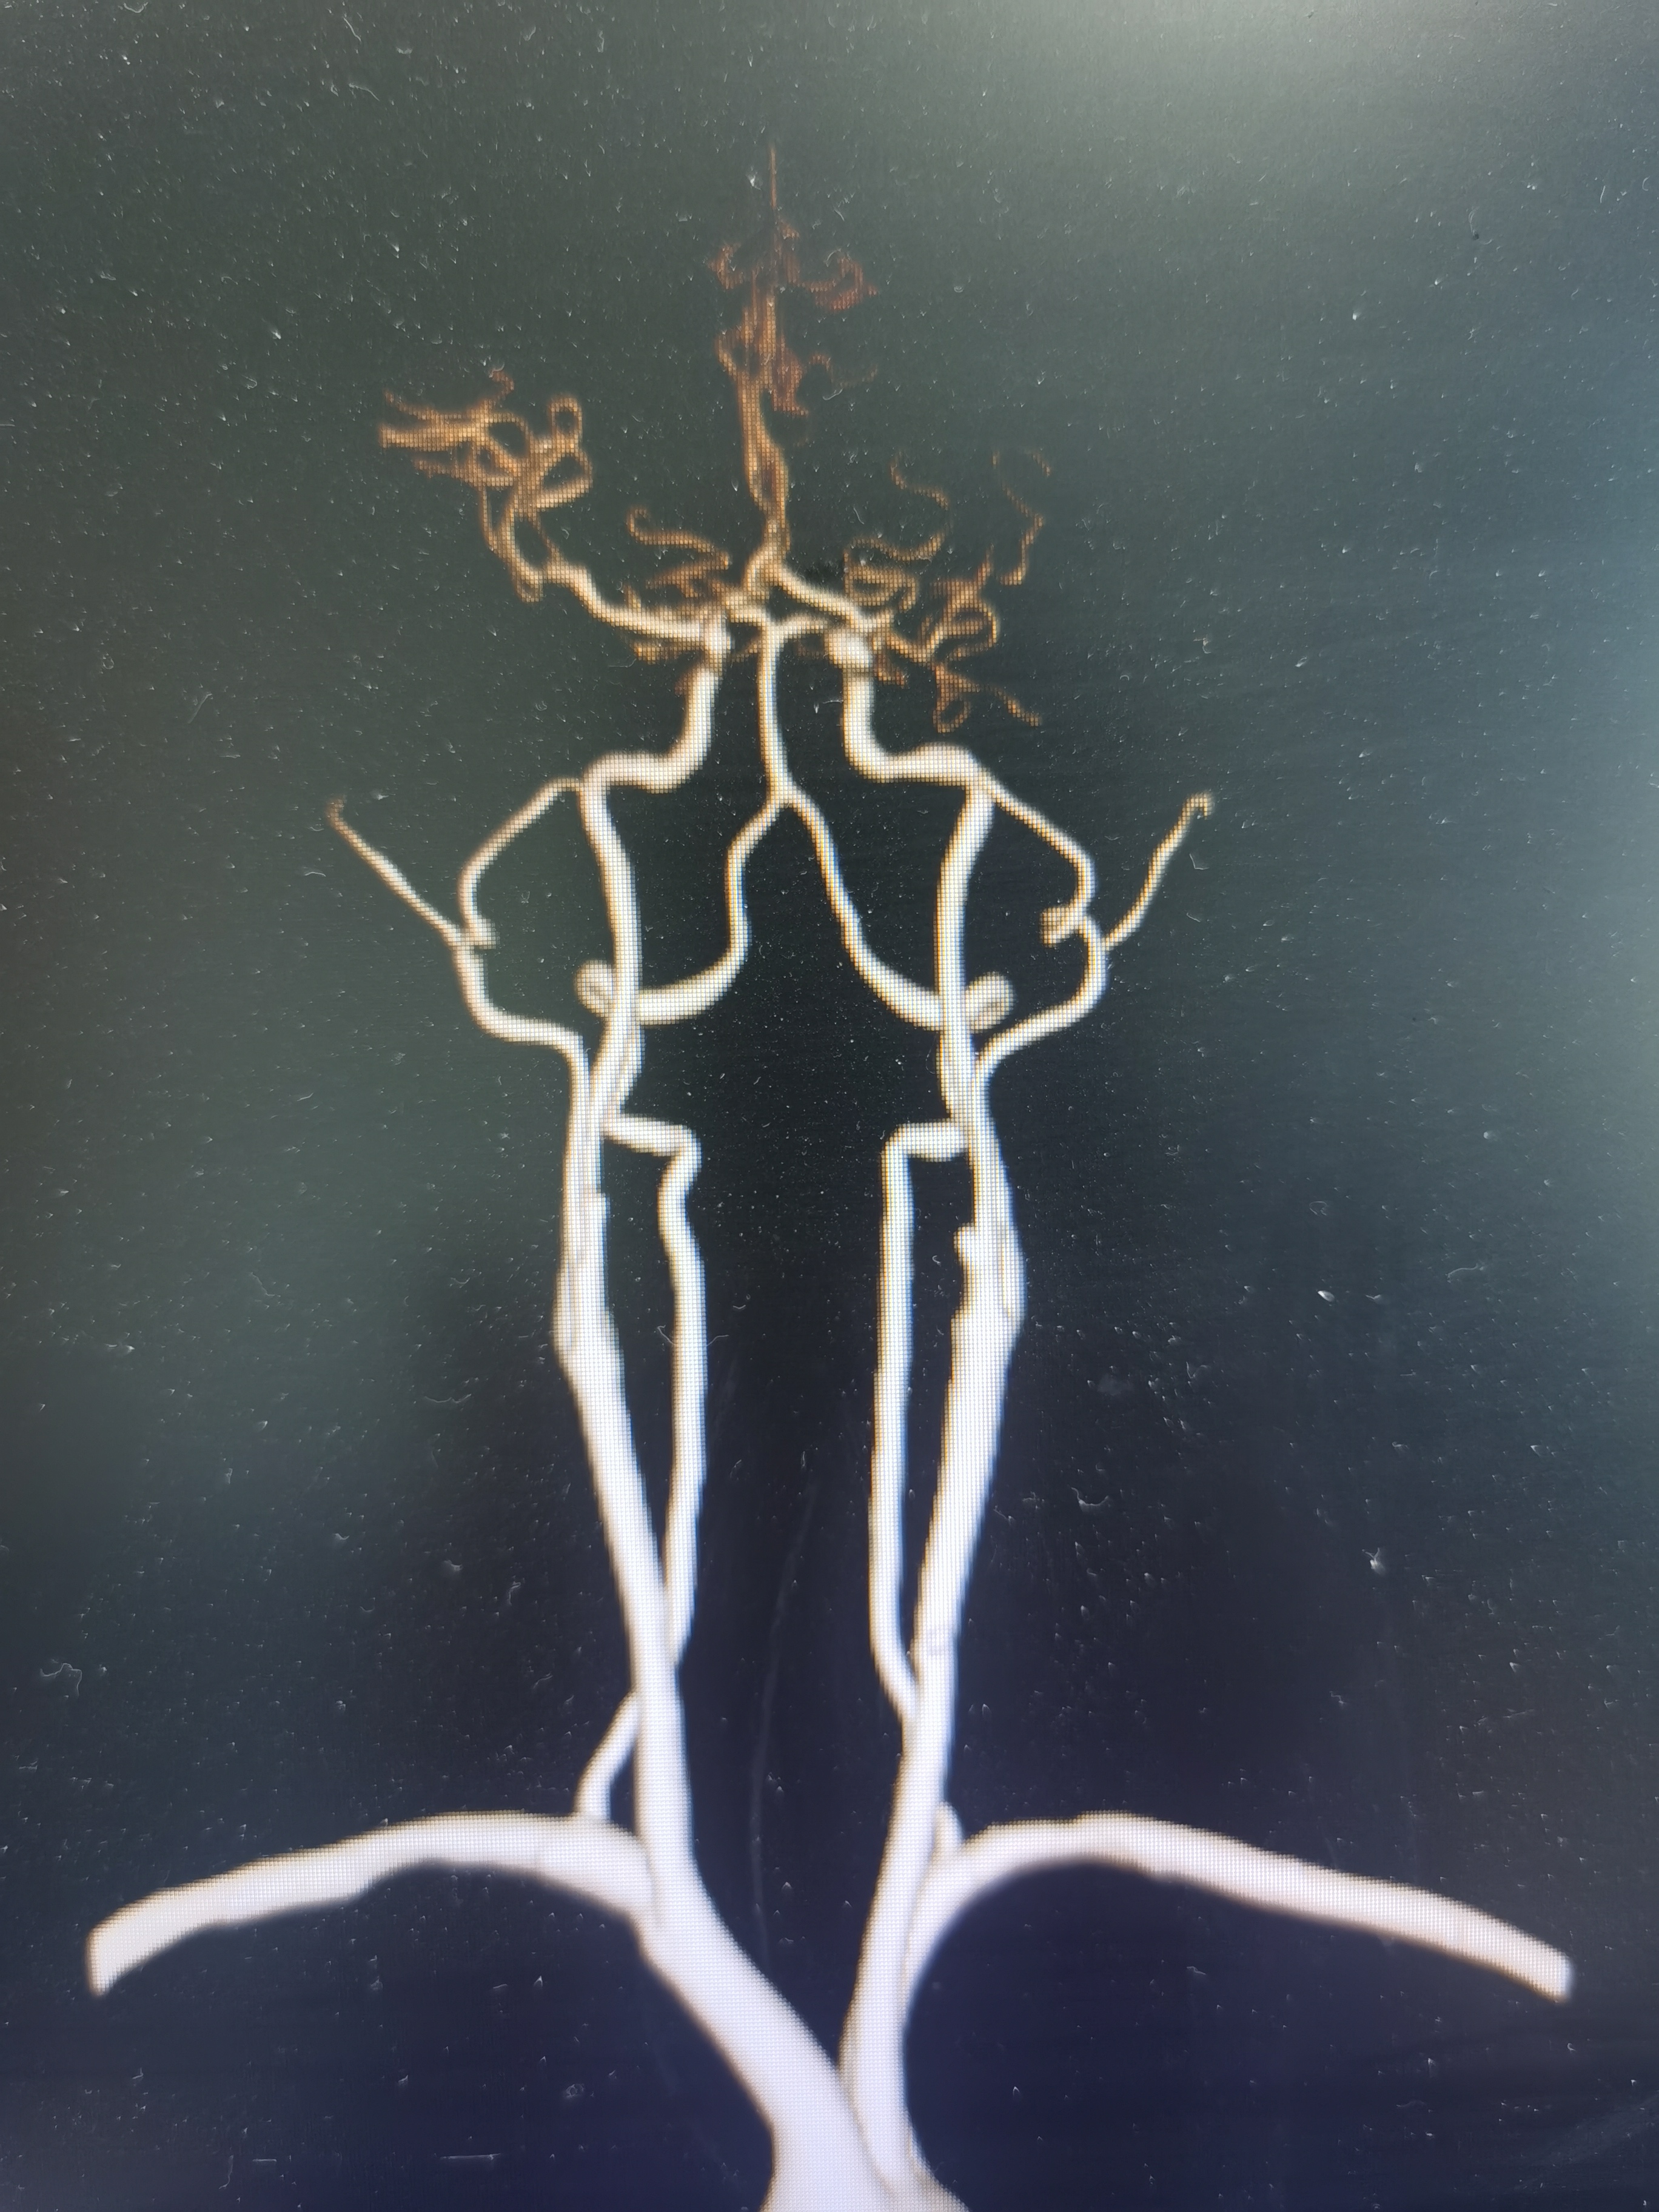

全麻后,将8F导引导管及中间导管顺利到位,建立路径,在路径图下微导丝携微导管顺利通过病变。

微导管确认位于真腔,交换入Transend300导丝。

2.0/15球囊扩张闭塞处。

扩张后造影见近端显影,远端血管仍闭塞。

将球囊前送,再次加压扩张。

扩张后造影见血管再通,血流通畅。

侧位造影见血流通畅。

观察15分钟后造影血流通畅,未见夹层及明显弹性回缩。

复查造影见颅内狭窄解除,血流通畅,遂未再植入支架,撤出导丝及各级系统,结束手术。患者麻醉苏醒顺利,无新发神经系统症状,给予替罗非班持续泵入,监测生命体征,控制血压避免再灌注损伤。

术前术后对比

1、本例患者系因左侧大脑中动脉急性闭塞出现左侧半球梗死,系责任血管。

2、造影评估见左侧大脑中动脉起始段闭塞,但动脉晚期可见远端血管返流显影,考虑闭塞段较短,且为新近闭塞,具备介入治疗指征。

3、球囊扩张后血管狭窄解除,无夹层及弹性回缩,遂未再植入支架,术后继续药物治疗,定期随访。